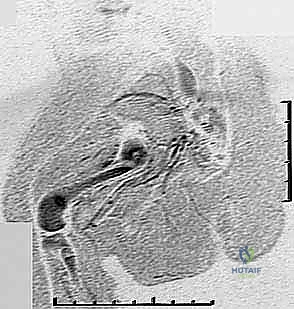

بعد التأكد من استقرار مفصل الورك والركبة، تبدأ مرحلة التطويل. يستخدم الدكتور هطيف أحدث التقنيات العالمية في صنعاء:

* المثبت الخارجي (Ilizarov / TSF): جهاز حلقي يثبت حول الساق، يتم من خلاله إجراء قطع عظمي دقيق (Corticotomy). يقوم الأهل بلف صواميل الجهاز يومياً بمقدار 1 ملم، مما يحفز الجسم على بناء عظم جديد في الفجوة (Distraction Osteogenesis).

معرض الصور السريرية لمراحل التثبيت والتطويل:

معرض إضافي لصور الأشعة والمتابعة الدقيقة للحالات: